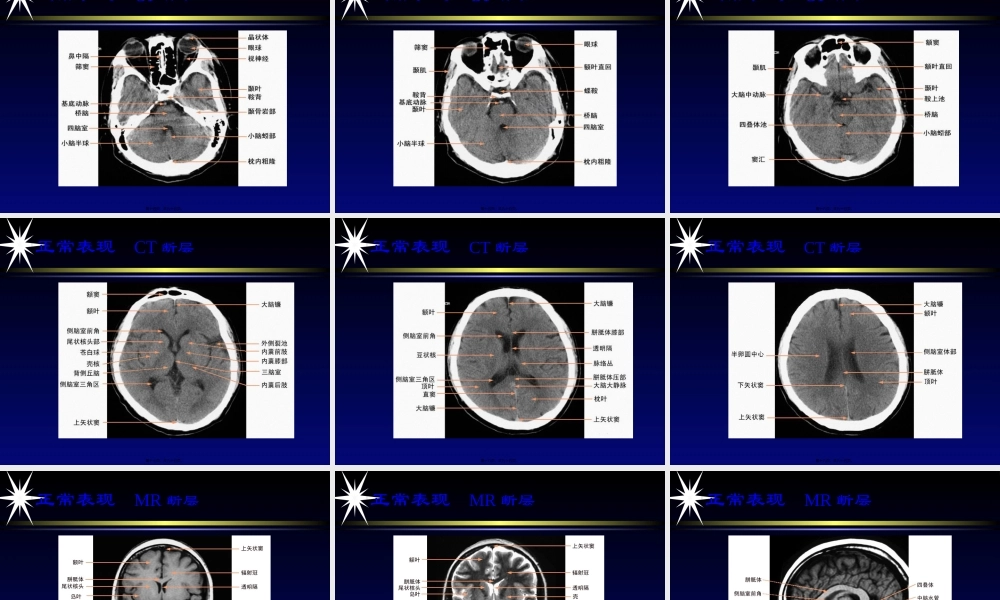

中枢神经系统影像学〔一〕中枢神经系统影像学〔一〕长安新安医院放射科李士光第一页,共九十五页。第一节检查技术第一节检查技术第二页,共九十五页。检查技术检查技术普通X线摄影数字减影血管造影计算机体层摄影磁共振成像技术第三页,共九十五页。检查技术普通X线摄影检查技术普通X线摄影头颅平片简单、经济第四页,共九十五页。检查技术普通X线摄影检查技术普通X线摄影常规摄影位置头颅侧位头颅正位第五页,共九十五页。检查技术数字减影血管造影检查技术数字减影血管造影动脉期动脉期颈内动脉造影(20°正位)颈内动脉造影(侧位)第六页,共九十五页。检查技术数字减影血管造影检查技术数字减影血管造影动脉期动脉期椎动脉造影(20°正位)椎动脉造影〔侧位〕第七页,共九十五页。检查技术计算机体层成像检查技术计算机体层成像常用CT检查方法又称平扫,为非增强扫描第八页,共九十五页。检查技术磁共振成像技术检查技术磁共振成像技术概述MRI的优点:对人体无电离辐射损伤、平第九页,共九十五页。检查技术磁共振成像技术检查技术磁共振成像技术MR图像特点数字化图像多参数成像多方位成像流动效应第十页,共九十五页。检查技术磁共振成像技术检查技术磁共振成像技术常用脉冲序列自旋回波〔SE〕:用于获取T1WI快速自旋回波〔FSE〕:用于获取T2WI和PDWI梯度回波〔GRE〕:主要用于获取T1WI和T2*WI,2D和3DMRA成像等反转恢复〔IR〕:主要用于脂肪抑制液体衰减反转恢复〔FLAIR〕:是IR序列的一种特殊类型,主要用于抑制脑脊液信号而使T2高信号病变显示得更清楚第十一页,共九十五页。MRI检查方法根本检查方法:检检查技术磁共振成像技术检查技术磁共振成像技术第十二页,共九十五页。第二节正常影像解剖第二节正常影像解剖第十三页,共九十五页。正常表现CT断层正常表现CT断层第十四页,共九十五页。正常表现CT断层正常表现CT断层第十五页,共九十五页。正常表现CT断层正常表现CT断层第十六页,共九十五页。正常表现CT断层正常表现CT断层第十七页,共九十五页。正常表现CT断层正常表现CT断层第十八页,共九十五页。正常表现CT断层正常表现CT断层第十九页,共九十五页。正常表现MR断层正常表现MR断层第二十页,共九十五页。正常表现MR断层正常表现MR断层第二十一页,共九十五页。正常表现MR断层正常表现MR断层第二十二页,共九十五页。正常表现MR断层正常表现MR断层第二十三页,共九十五页。正常表现脊...